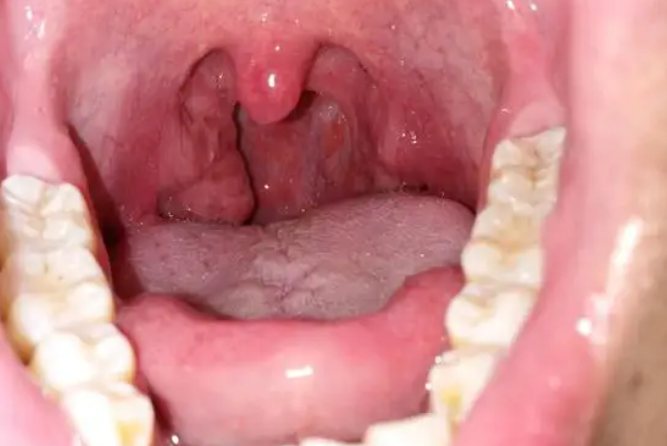

1、扁桃体周围蜂窝织炎

扁桃体周围蜂窝织炎临床表现为咽部严重充血红肿,扁桃体增大、伴有脓性渗出液,通常不伴悬雍垂偏斜和张口困难,患者自觉咽部疼痛明显。